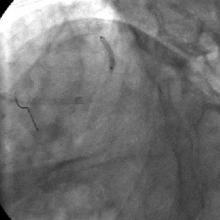

3) LAD: Ostial CTO ( Figure 2) with collaterals from RCA and LCX (Figure 3).

The left system was engaged with XB 3.5 guiding catheter through the femoral route. With the help of a 1.1x1.5mm CTO balloon, we directed a Shinobi guidewire towards the ostial LAD lesion (Figure 4). After making sure that the guidewire was pointing towards the CTO with its tip at the CTO lesion, we used the torquer to gently twirl the guidewire without forcing or overly manipulating it and allowed the guidewire to find its own way through the CTO by patiently twirling it at the lesion site. Within a few minutes, the guidewire jumped through the CTO lesion (Figure 5) and then through the lesion with the help of the CTO balloon (Figure 6). The path was first confirmed by engaging the RCA from the radial approach and injecting dye into the RCA (Figure 7). The CTO was then predilated with a 2.0x30mm Sapphire balloon (Figure 8 and Figure 9) and stented it with a 3.0x36mm DES (Figure 10 and Figure 11). Later the RCA was engaged with a JR 3.5 guiding catheter. A Cougar guidewire crossed the RCA lesion that was directly stented with a 3.0x13mm BMS (Figure 12 and Figure 13).